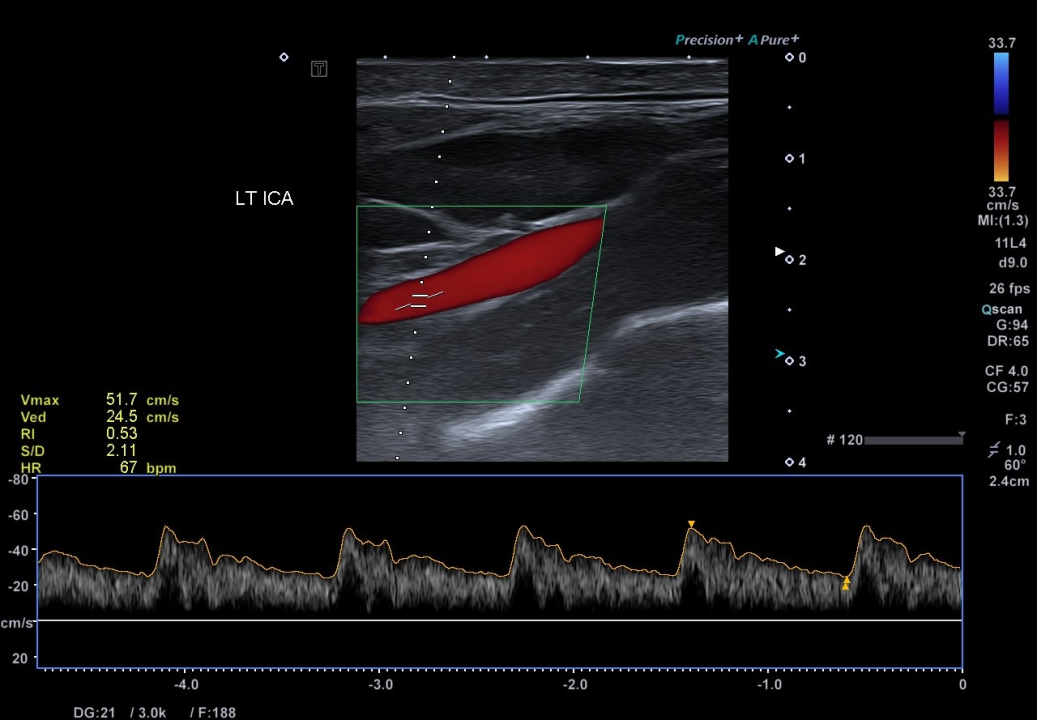

Povodom svjetskog dana zdravlja o aterosklerozi kao najvećim javnozdravstvenim problemom i vodećim uzrokom bolesti i smrti na svijetu, pričali smo s doktorom specijalistom neurologije dr.